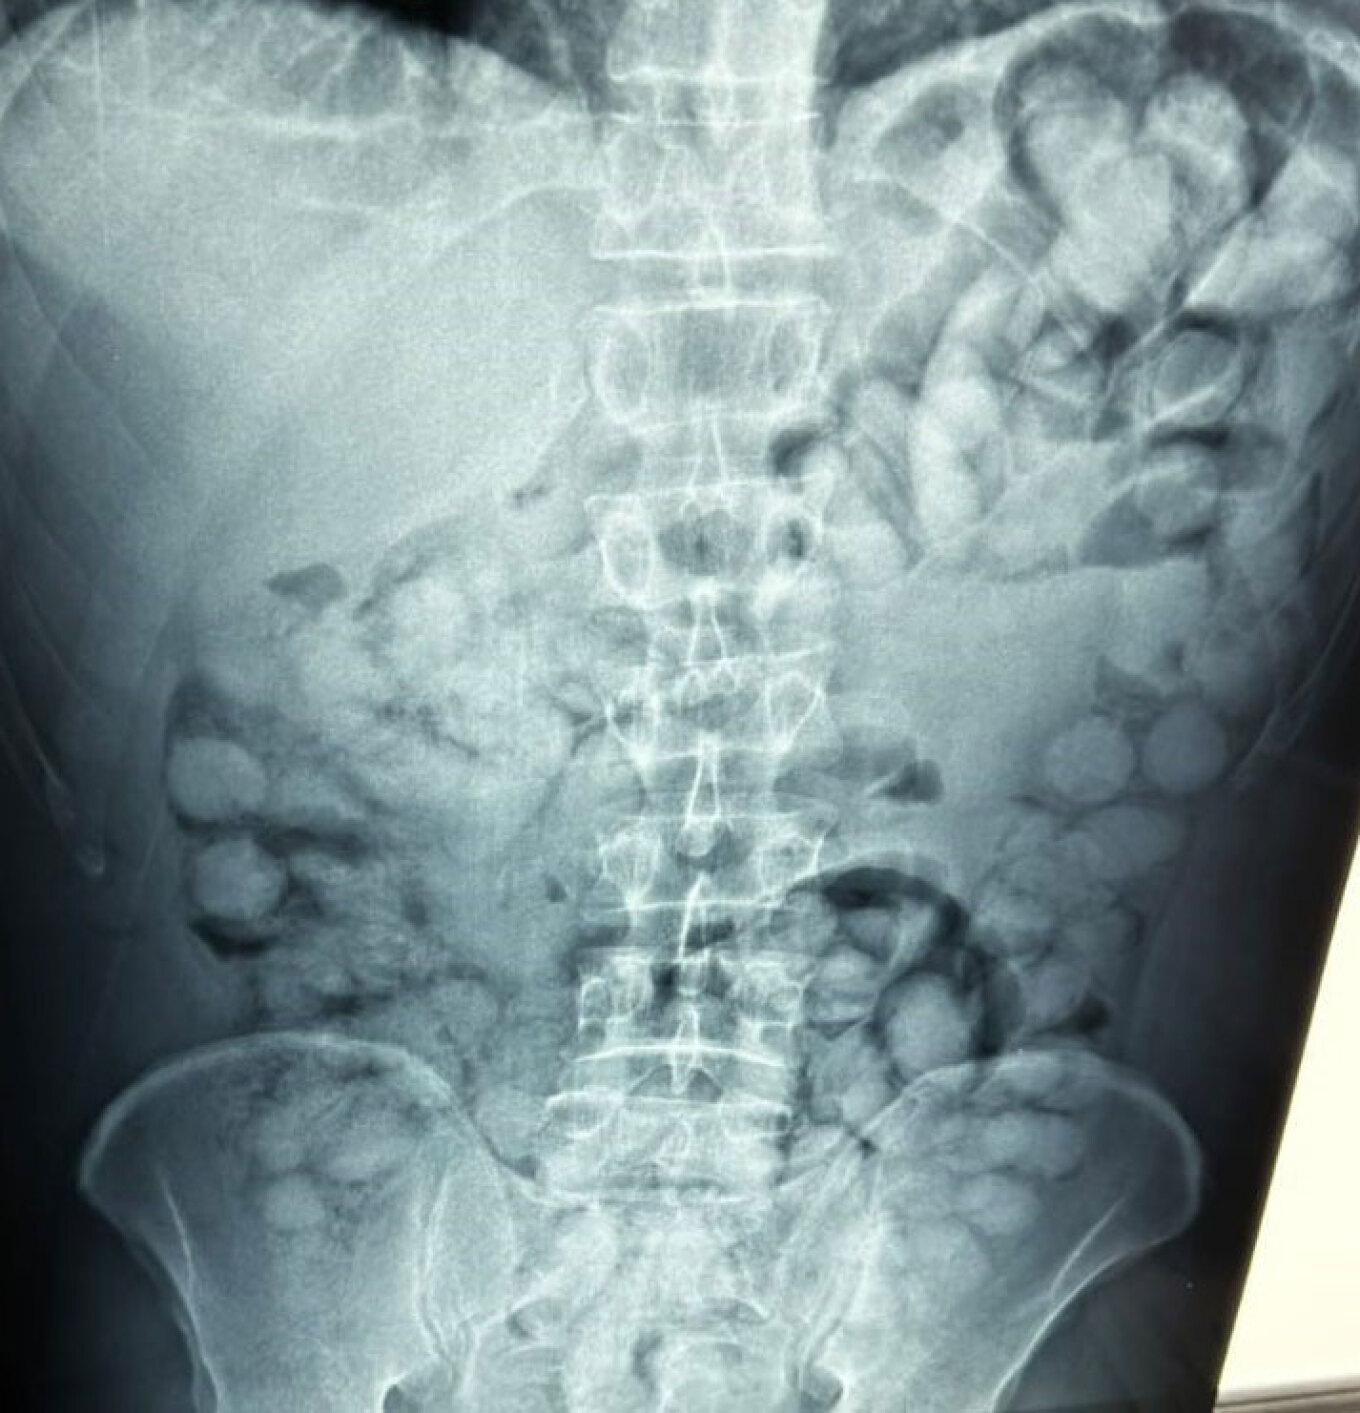

Ένας άνδρας, από τη Βραζιλία, συνελήφθη το πρωί στο αεροδρόμιο «Ελευθέριος Βενιζέλος», κατηγορούμενος ότι είχε καταπιεί σημαντική ποσότητα κοκαΐνης.

Σύμφωνα με την Αστυνομία, ο άνδρας έφτασε στην Αθήνα, μέσω Παρισιού και στον έλεγχο που διενεργήθηκε, διαπιστώθηκε ότι είχε καταπιεί περίπου 100 συσκευασίες κοκαΐνης.